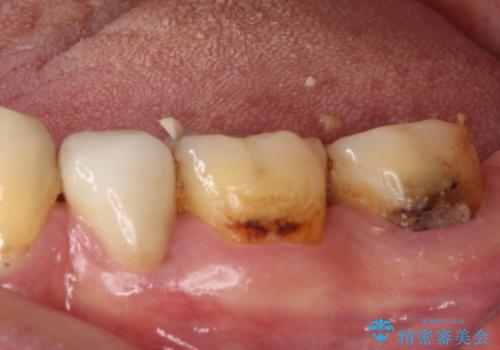

- 奥歯がしみるとのことで来院された患者様です。

診査をしたところ、目視でも明らかな、とても大きなむし歯があありました。

既に治療により詰め物が装着されている歯であったため、オールセラミッククラウンによる補綴治療を選択することとしました。